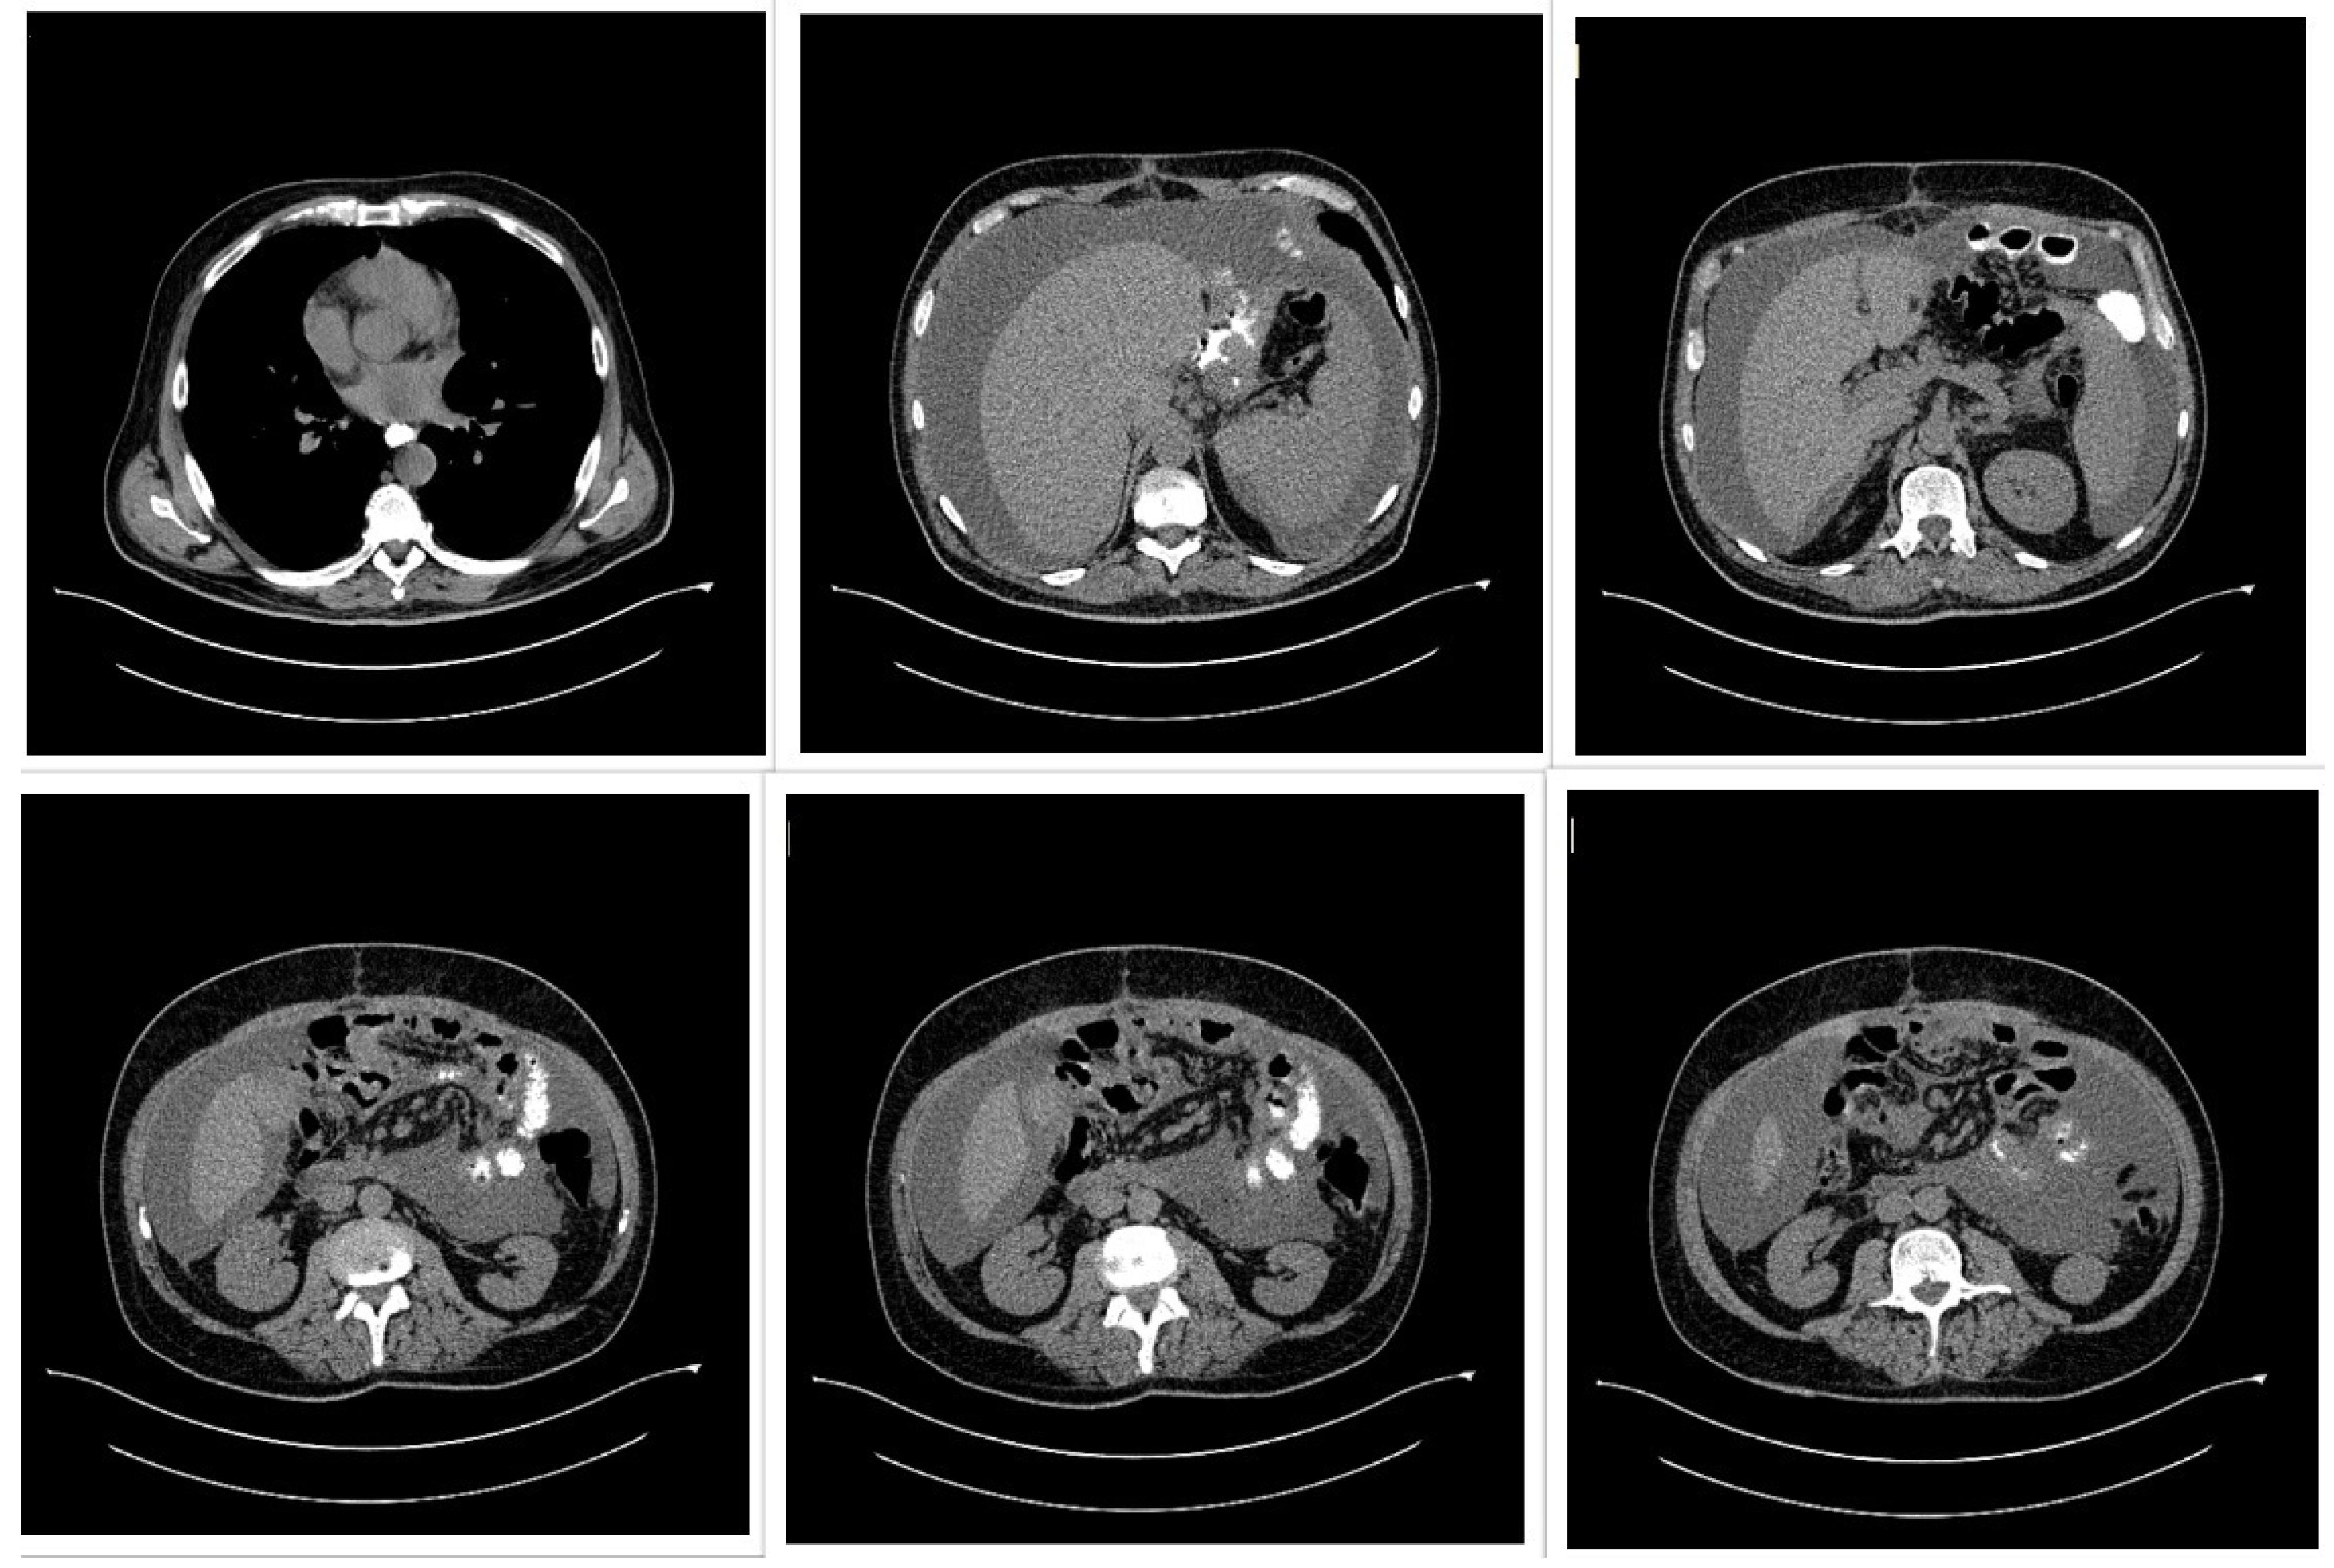

A 50-year-old male patient (Figure 2) with associated pathologies (arterial hypertension, mitral insufficiency, heart failure NYHA grade II, chronic venous insufficiency, and history of superficial phlebitis on the lower limbs) was admitted in the hospital clinically presenting varicose veins, with sinuous and dilated aspect, bilaterally compressible (Figure 3), at the level of the lower limbs, and pale tegument. Paraclinically, the following blood tests were requested: the biochemical profile, coagulation tests and complete blood count, from which the most critical findings were the following parameters: Quick time 73% (WRR. 190–148%), prothrombin 14.3 s (9.4–12.5 s), fibrinogen 400 mg/dL (200–393 mg/dL), hemoglobin 5.1 g/dL (13.6–17.2 g/dL), lymphocytes’ number 0.6 × 101/miL (0.8–3.8 × 101/mi) and lymphocytes percentage 12.2% (20–40%), red blood cells’ number 3.08 × 106/miL (4.5–5.9 × 106/miL), hematocrit 18.7% (39–51%), erythrocyte volume 60.6 fl (80–100 fl) and RDW-CV 17.2% (11.6–14%). Increased attention was paid to the severe anemia (Hb = 5.1 g/dL) detected, after which a gastroenterological consultation was requested, the gastroscopy revealing a proliferative ulcerated process over the greater curvature of the stomach, with an approximate dimension of 10 cm. In the meantime, a thoracic CT and abdominal ultrasound were performed as well (Figure 4): the chest CT revealed a bulge of the right lower cardiac arch and pulmonary hilum increased in volume, without processes of pulmonary condensation. In contrast, the abdominal ultrasound showed marked meteorism and a thin layer of perisplenic and perihepatic fluid. In light of paraclinical and clinical findings, it was then decided to intervene surgically, and during the procedure, a voluminous gastric neoplasm was found, invading the transverse colon, together with peritoneal carcinomatosis, parietal invasion, and neoplastic ascites. Therefore, the surgical team decided to practice subtotal gastrectomy, HoffmeisterFinsterer gastro-jejunal anastomosis, omentectomy, lysis of adhesions and subhepatic drainage. Two specimens were collected: a gastric tumor with epiploon and a second one with the peritoneal carcinomatosis, and eventually the histopathological examination came to the diagnosis of a muco-secreting gastric carcinoma, diffused, with cells in “seal ring”, mildly differentiated G3 with lymph node and peritoneal metastasis. Postoperatively, antibiotic and analgesic treatment, TEP and DVT prophylaxis, toilet and wound dressing were instituted, with favorable evolution and suppression of the drain tube and suture threads. Finally, the patient was discharged with a good general condition, presenting appetite, afebrile, present T.I, considered surgically cured, with the recommendation of an oncological consultation and a second check-up at 30 days apart. Indeed, a month later, the patient was again admitted to the hospital, presenting with nausea, loss of appetite and abdominal distention; therefore, an abdominal and pelvic CT-scan with contrast media was requested as a paraclinical investigation. The scan confirmed a good functioning of the gastroenteric anastomosis performed in the previous operation, but a large perihepatic and perisplenic ascites between intestinal loops and bilateral parieto-colic was found, and for this reason a paracentesis was decided to perform, via which approximately two liters of ascitic fluid was evacuated. The patient was then referred to oncology, in order to initiate the appropriate chemotherapeutic treatment and discharged with improved general conditions.

Figure 4.

Thoracic and abdominal computed tomography (CT) scan showing a voluminous gastric tumor compressing the inferior vena cava, associated with para-aortic adenopathy, and without hepatic, peritoneal, or pulmonary metastases.